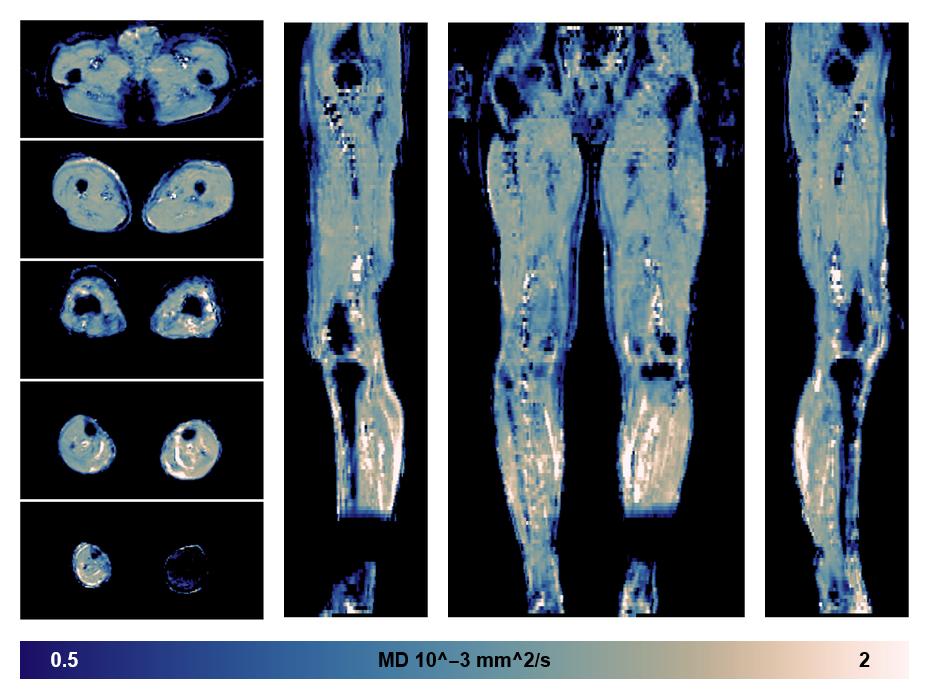

• Mean diffusivity

IVIM corrected whole leg muscle mean diffusivity obtained from diffusion tensor imaging.